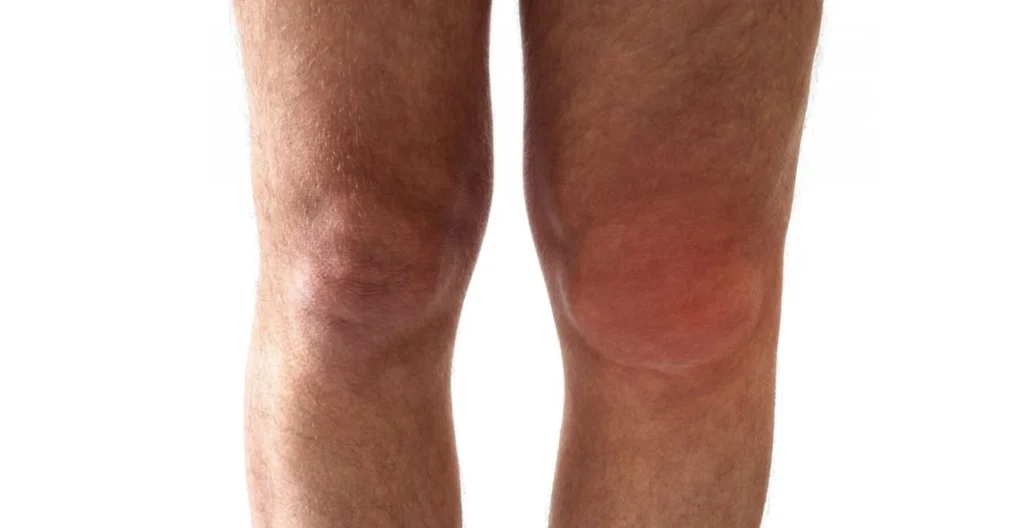

B. Swelling and Warmth in Joints

When the joint’s cartilage becomes irritated, your body floods the area with synovial fluid to cushion the impact. That’s why joints may look puffy or feel warm to the touch. It’s the inflammation doing its job — just a bit too enthusiastically.

Warm compresses and light massage may help ease that tight, full feeling. Doctors sometimes confirm inflammation through joint fluid analysis or MRI scans if it persists.

Pro Tip: If one knee or hand swells but the other doesn’t, it’s probably mechanical OA inflammation — not autoimmune childhood arthritis or rheumatoid arthritis, which usually affects joints symmetrically.

- Swelling that doesn’t subside after rest

- Redness or warmth around joints (possible infection)